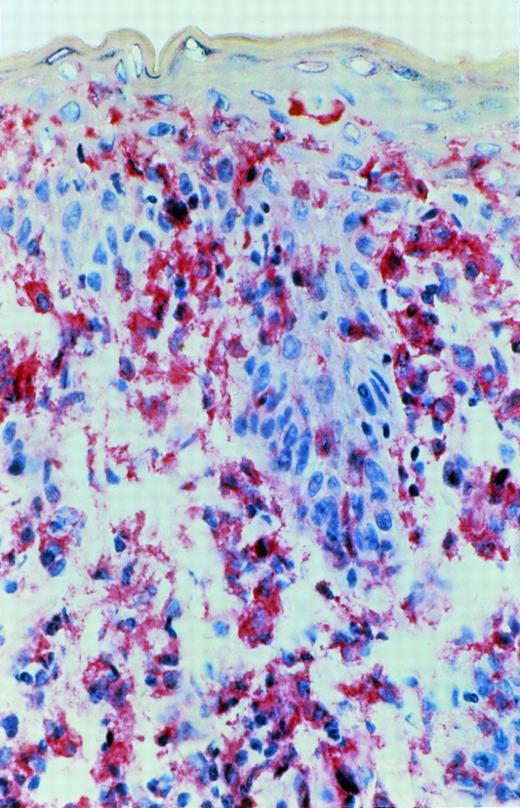

Immunoreactivity for IL-15 was detected in epidermal cells, especially in the basal layer of the epidermis, in cells with a dendritic morphology in the dermis and in mononuclear cells. This immunoreactivity could be blocked by exogenous recombinant IL-15. In early CTCL lesions (patches) (n = 5), immunoreactivity was strongest in the junction zone between epidermis and dermis where the lymphocytic infiltrates show their highest densities (Fig 7). In advanced lesions (plaques) (n = 5), immunoreactivity was also detected in deeper parts of the dermis in areas heavily infiltrated by mononuclear cells (Fig 8).

A more advanced CTCL lesion (plaque stage): immunoreactivity for IL-15 after APAAP staining was detected in the junctional area and in deeper parts of the dermis heavily infiltrated by mononuclear cells.

In advanced lesions (plaques), IL-15 immunoreactivity was also detected in deeper parts of the dermis in areas heavily infiltrated by mononuclear cells (Fig 8). This can confirm our mRNA results, indicating that the dominant T-cell clone can produce the cytokine itself. It is possible that autocrine IL-15 production increases during tumor progression and that CTCL cells therefore lose their dependency on the cutaneous microenvironment.